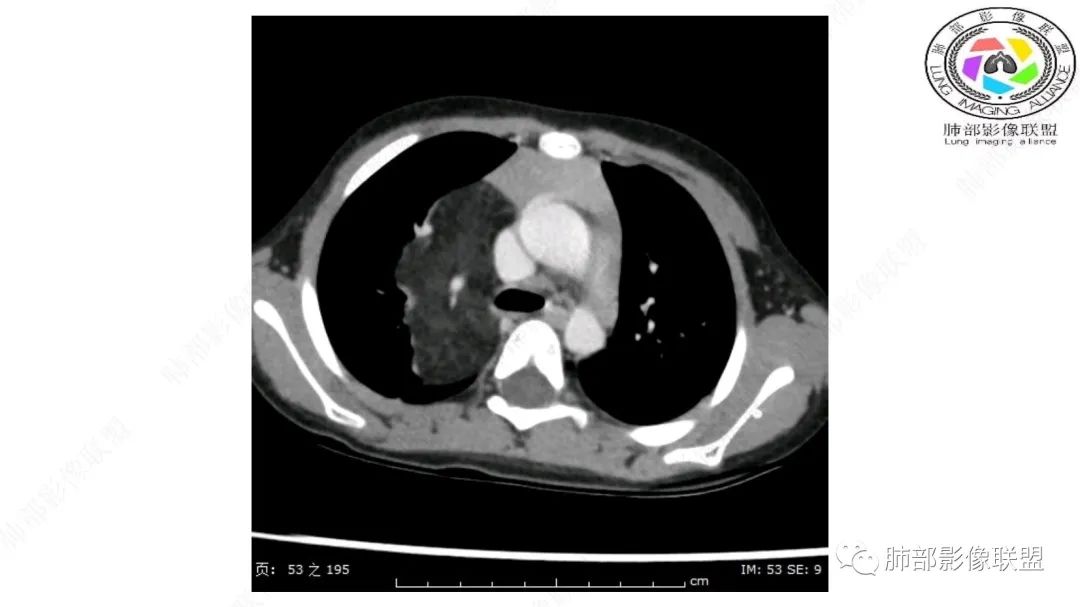

右上纵隔混杂密度肿块,边缘光整,与纵隔分界清,其内多发脂肪密度,增强无明显强化,其内血管穿行,考虑纵隔脂肪母细胞瘤,鉴别畸胎瘤,脂肪肉瘤。

右纵隔团状,密度不均,脂肪密度为主,内可见腺体样组织,类似乳腺,病灶边缘有分叶,与胸腺关系密切,增强后血管穿行。考虑胸腺脂肪瘤(不典型垂乳征),鉴别畸胎瘤。

可以看到造影剂进入的丛状结构

密度不均,非纯脂肪成分。斑片状密度略高区域有轻度填充式强化。

病灶属于交界区,主体位于肺内,占位效应明显,前方突入胸壁,胸腺受压变形,胸膜显示欠清楚;病灶包绕上叶肺动脉;似乎有体动脉供血。符合肺内的点:包绕上叶肺动脉分支;符合纵隔的点:前方似乎突入胸壁,与胸腺关系比较密切,但是与上腔静脉的关系提示病灶不支持纵隔来源,前纵隔的常规会将上腔静脉受压后移、外移,这是不符合的。

内部血管明显,部分病灶密度增高,单纯脂肪瘤不支持。可惜的是:没有提供CT值:是否强化?如果强化,警惕恶性;胸腺肯定不符合,胸腺会将上腔静脉朝后推移。

2.肺动脉穿行也许是肺内来源最重要支持点!

脂肪母细胞瘤由成熟程度不同的脂肪组织、纤维间隔、黏液基质、小血管丛等间质成分组成,以脂肪组织与黏液样基质为主,其影像学表现取决于上述组织成分。典型的CT和MRI表现为:前后纵隔均可发生,常见于前纵隔;肿块大小不一,直径多在3cm~7cm,密度均匀,CT值呈水样或脂肪密度,脂肪组织密度或信号为主的肿块,其内密度或信号不均匀,可见粗细不一的分隔影,且有结节、片状影,后者可呈轻中度强化;结节状肿瘤包膜完整;弥漫性者包膜不明显,常呈浸润性生长;周围结构为受压和推移改变,可有少量胸腔积液,淋巴结无增大。